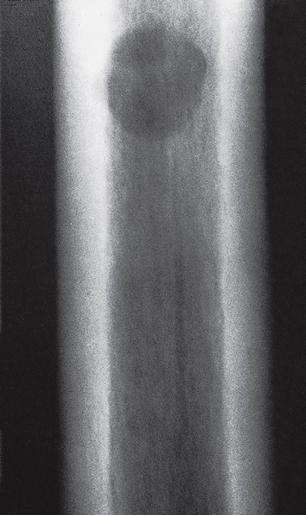

Focal reduction in density is usually referred to as a ‘lytic area’ or an area of ‘bone destruction’.